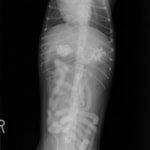

4歳 アメリカンショートヘアー

主訴:3日前から嘔吐が続き、食欲も落ちてきたのこと。

対症療法(症状に対する治療)に反応しないため、精査を実施。

一般血液検査:問題なし

単純レントゲン検査:胃内ガス陰影・腸内ガスが少量認められる。

嘔吐が改善しないため、消化管バリウム造影検査を実施。

以下、

消化管バリウム造影レントゲン

バリウム造影3時間経過するも、胃内からバリウム排泄なく同日内視鏡検査を実施。

内視鏡検査結果:内視鏡下にて、バスケット鉗子を用いて摘出。

症例は、机の上に置いていたピスタチオのお菓子を誤飲していました。その後の経過は良好です。本症例は、内視鏡下にて摘出ができましたが、球状・立体などの大きな異物は、腸の途中で詰まりやすく、内視鏡下での摘出が困難な場合もあります。その際は、開腹下にて腸内の異物を摘出しなくてはなりません。動物たちは、思わぬ物を誤飲することがあります。お留守番時・就寝時は、誤飲をしやすい時間帯ですので注意しましょう。